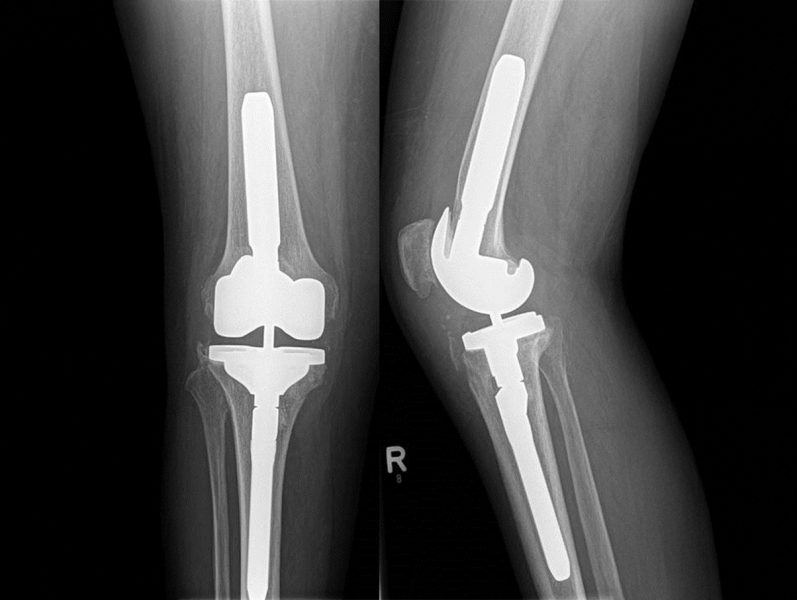

In unserer Abteilung werden primäre und Revisionsendoprothesen an Hüft –, Knie – und Schultergelenken durchgeführt.